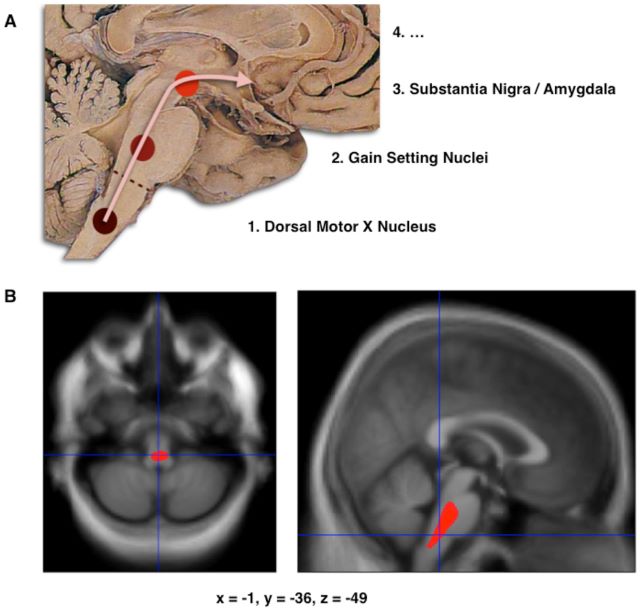

File:Journal.pone.0008247.g001.png. In Wikipedia

A. progression of Lewy body deposits in brain stem. B. Area brain volume reduction. Source: wikipedia.